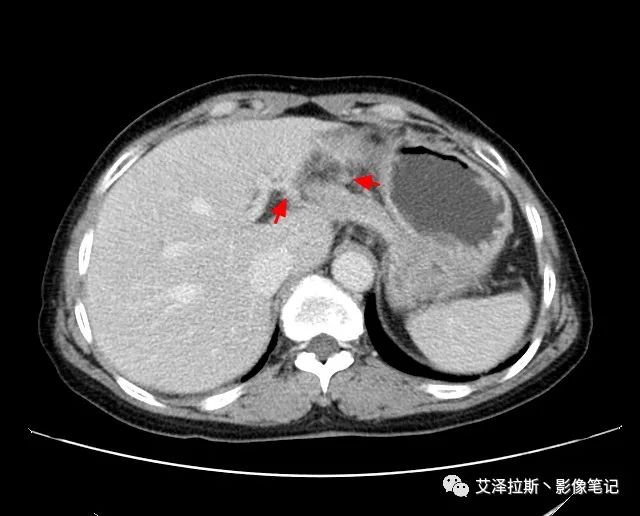

以下為累及的區域淋巴結,共計15個區域:

【影像所見】 胃竇部狹窄,胃壁環形增厚,小彎側見一巨大潰瘍,周圍伴“環堤征”,漿膜面不完整,胃周脂肪見網格狀條索影,病灶與肝臟左葉、胰腺鉤突脂肪間隙消失,增強掃描病灶明顯強化。引流區內約15個區域淋巴結受累。

【診斷意見】 胃竇部胃癌(T4N3期) 該病例腫塊突破漿膜層,與肝臟左葉、胰腺鉤突分界不清,脂肪界面消失,定為T4期; 受累及的淋巴結為15個區域,定為N3; 有無遠處轉移尚不明確,所以M期暫時無法確定。